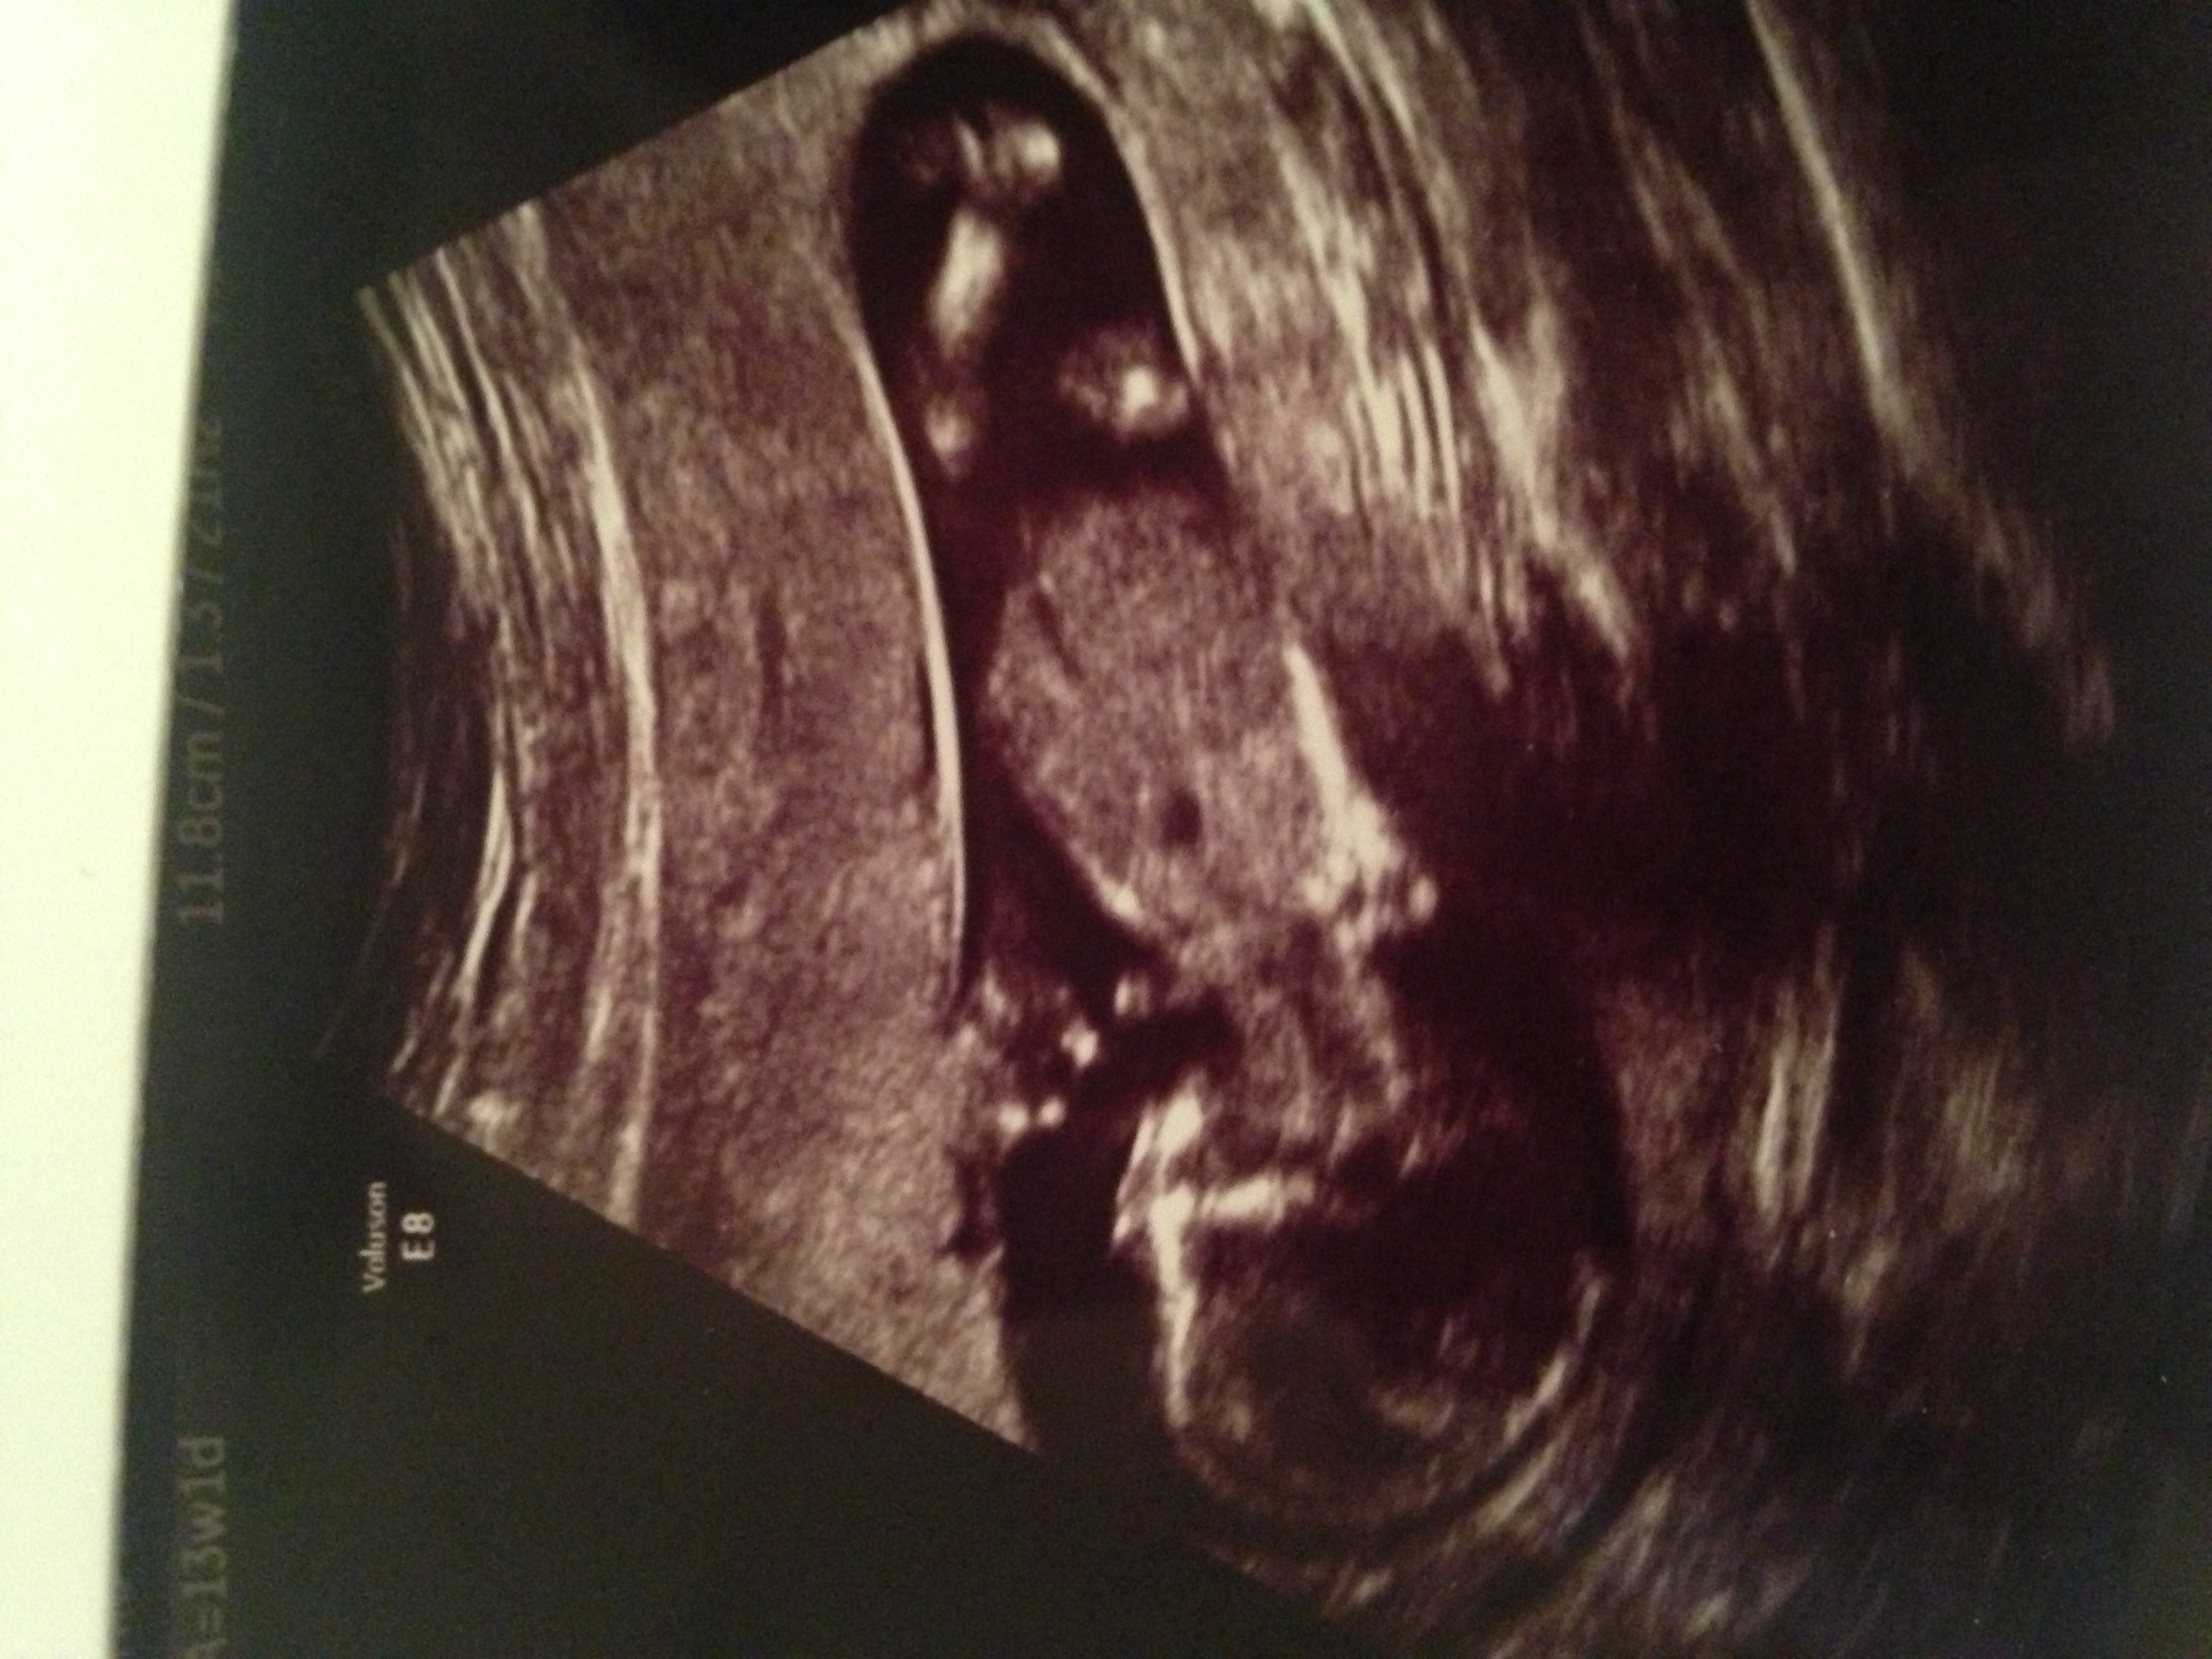

Attachment 19095. Can anyone take a guess at sex of baby?! Thanks x

No nub the baby has to be facing sideways but cute baby!

No gender clues.

It was worth a try! Thanks anyway x